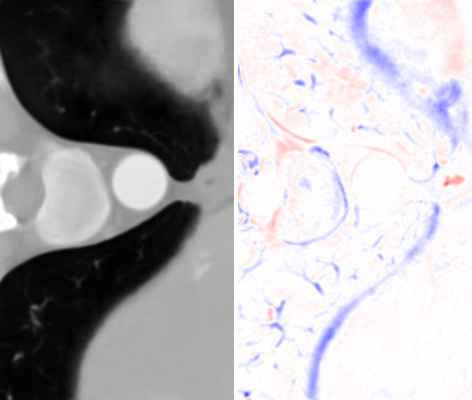

Refer to caption

(a) Isagz(x,y)superscriptsubscript𝐼𝑠𝑎𝑔𝑧𝑥𝑦I_{sag}^{z}(x,y)

(b) Icorz(x,y)superscriptsubscript𝐼𝑐𝑜𝑟𝑧𝑥𝑦I_{cor}^{z}(x,y)

(c) Iavgz(x,y)superscriptsubscript𝐼𝑎𝑣𝑔𝑧𝑥𝑦I_{avg}^{z}(x,y)

(d) Ifuse(x,y)subscript𝐼𝑓𝑢𝑠𝑒𝑥𝑦I_{fuse}(x,y)

Figure 4: (a) The axial slice generated from Isagsubscript𝐼𝑠𝑎𝑔I_{sag}. (b) The axial slice generated from Icorsubscript𝐼𝑐𝑜𝑟I_{cor}. Some details are better resolved by (a) and others by (b). Both of them exhibit directional artifact due to a lack of constraints in the (x,y) plane. This is resolved through RFN in (d), which refines their average Iavgsubscript𝐼𝑎𝑣𝑔I_{avg}, as shown in (c)